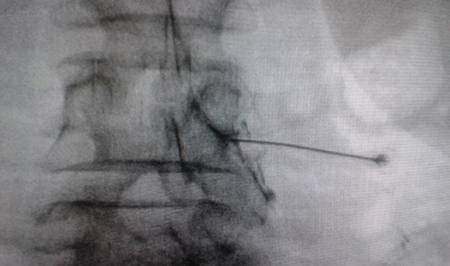

Figura 2